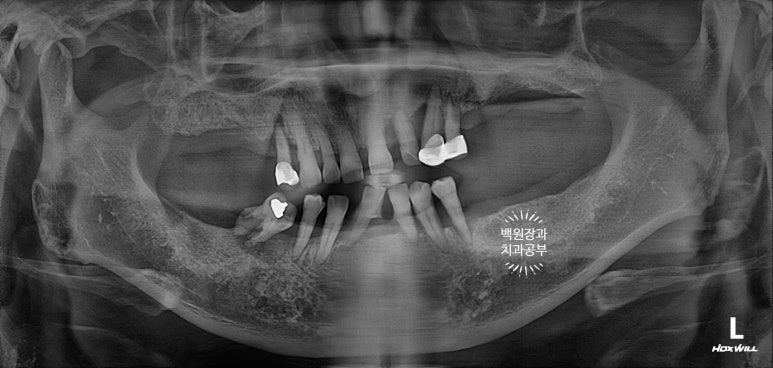

정면에서 찍어본 구강 내 사진 소견입니다.

다수의 치은연상치석, 치은연하치석이 침착되어 있고, 만성치주염으로 인해 치아가 제 위치를 상실하여,

치아의 병적이동 (pathologic migration)을 하고 있는 중이었죠.

풍치가 심해서 만성치주염을 오래 앓으신 분들은 치아 사이가 벌어져 심미적으로 불리한 모습을 많이 보이십니다.

게다가, 어금니들도 씹는 면끼리 물리지 못해서 이제 식사도 어려우신 상황이었어요.

파노라마 엑스레이상에서 많은 치아가 있어보이지만,

실제로 대부분의 치아는 많은 양의 치석이 침착되어 만성치주염의 주소견인 흔들림을 보여주고 있었습니다.